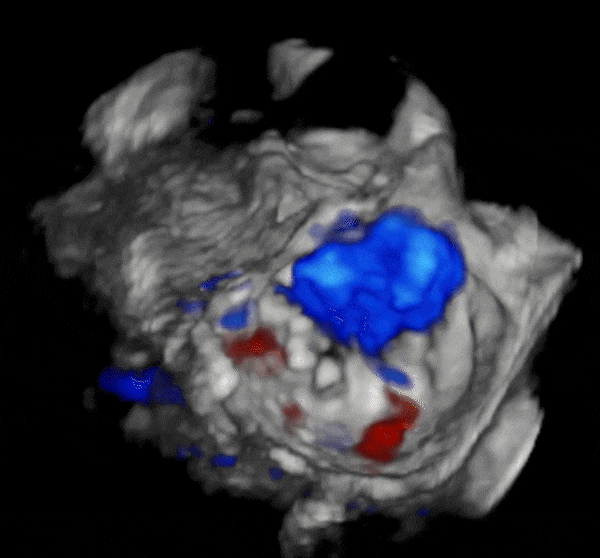

术前3D

心脏超声示左室增大,二尖瓣2、3区脱垂伴重度反流(腱索断裂),Carpentier分型Ⅱ型,典型Barlow综合征表现;二尖瓣开放面积5.0cm²,3区瓣环内径31mm,前叶长22mm、后叶17mm,前叶收缩期关闭瓣体部分呈拱形突向左房腔,瓣膜游离缘对合欠佳,可见腱索断裂,长度9mm;2区瓣环内径32mm,前叶长22mm、后叶10mm,前后叶均可脱垂;三尖瓣重度反流。CDFI示瓣口重度偏心性反流,反流束沿主动脉后壁走行,肺静脉收缩期可见反向频谱。